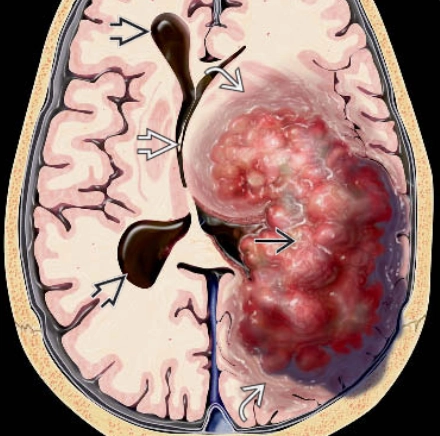

• U đám rối mạch mạc (Choroid Plexus Tumors)

• Ung thư biểu mô đám rối mạch mạc (Choroid Plexus Carcinoma)